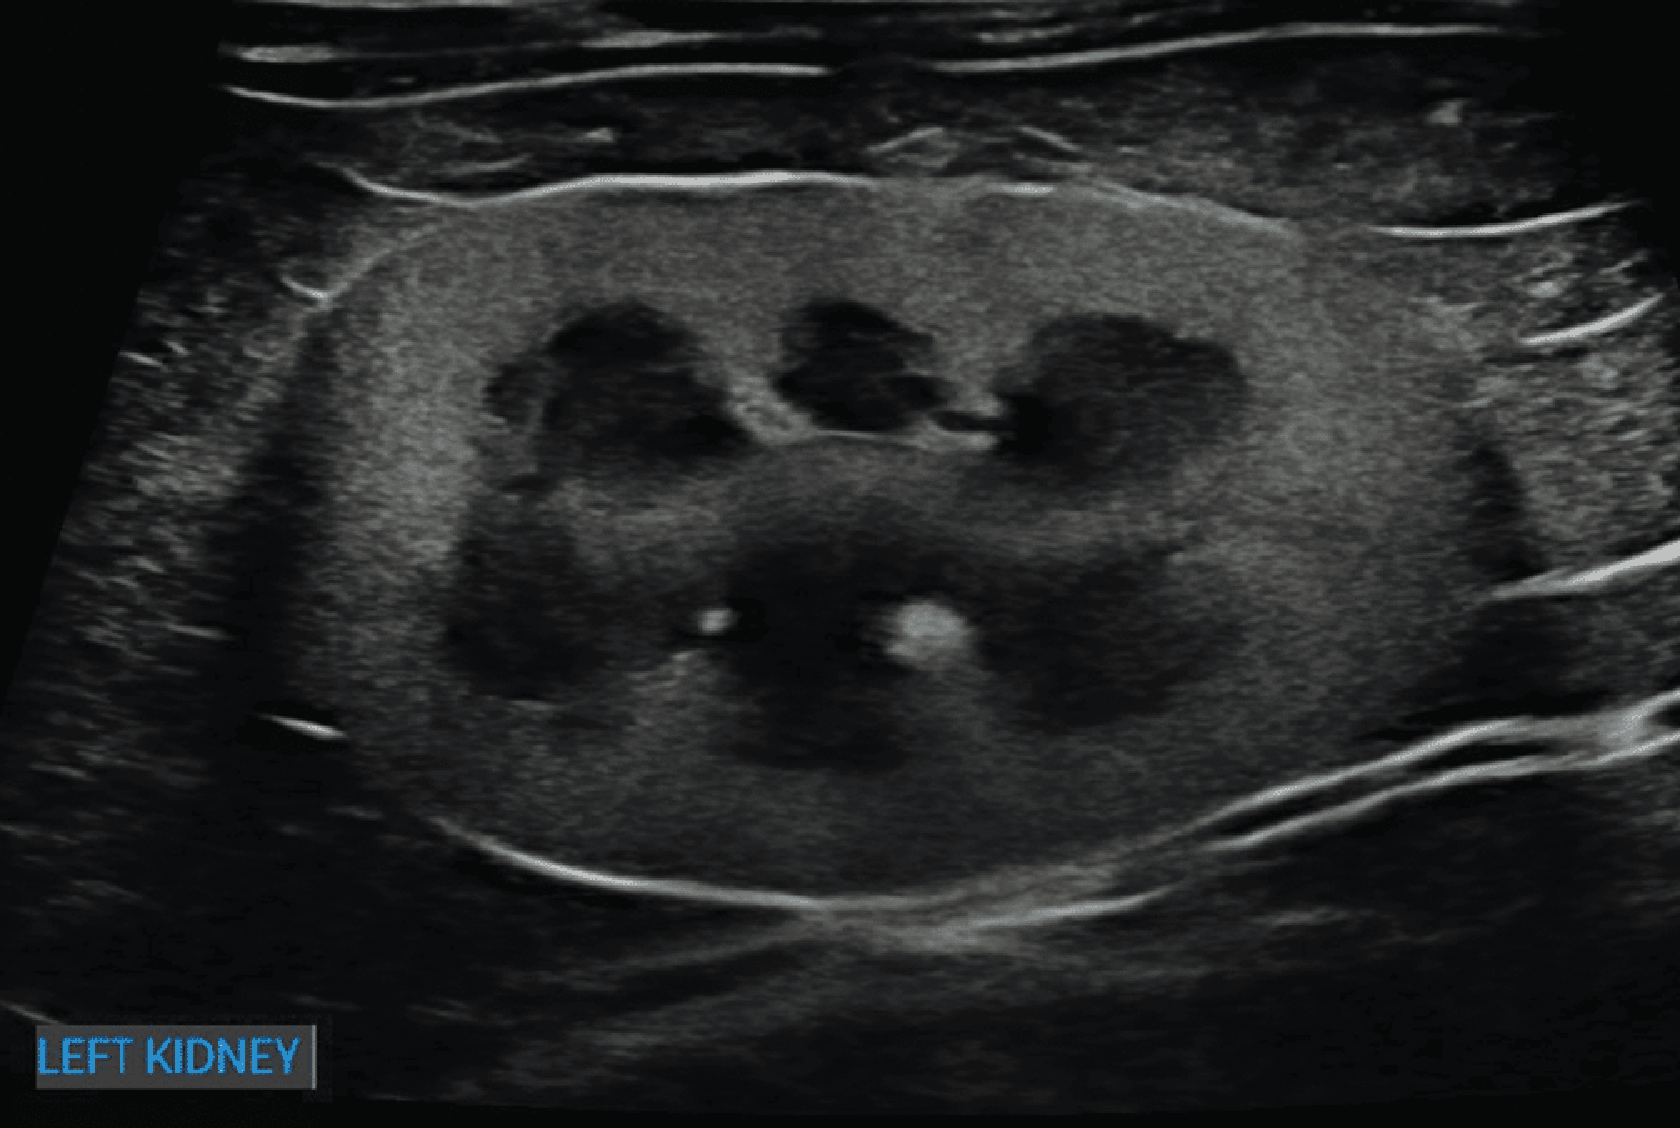

Ryc. 3. Obraz w projekcji strzałkowej lewej nerki kota, przedstawiający wyraźnie zwiększoną echogeniczność kory nerkowej, skutkującą wzmożonym zróżnicowaniem korowo-rdzeniowym, co jest najbardziej zgodne z rozpoznaniem lipidozy kanalikowej. To zjawisko u kotów często powoduje, że nerki są hiperechogeniczne w stosunku do wątroby i/lub śledziony.